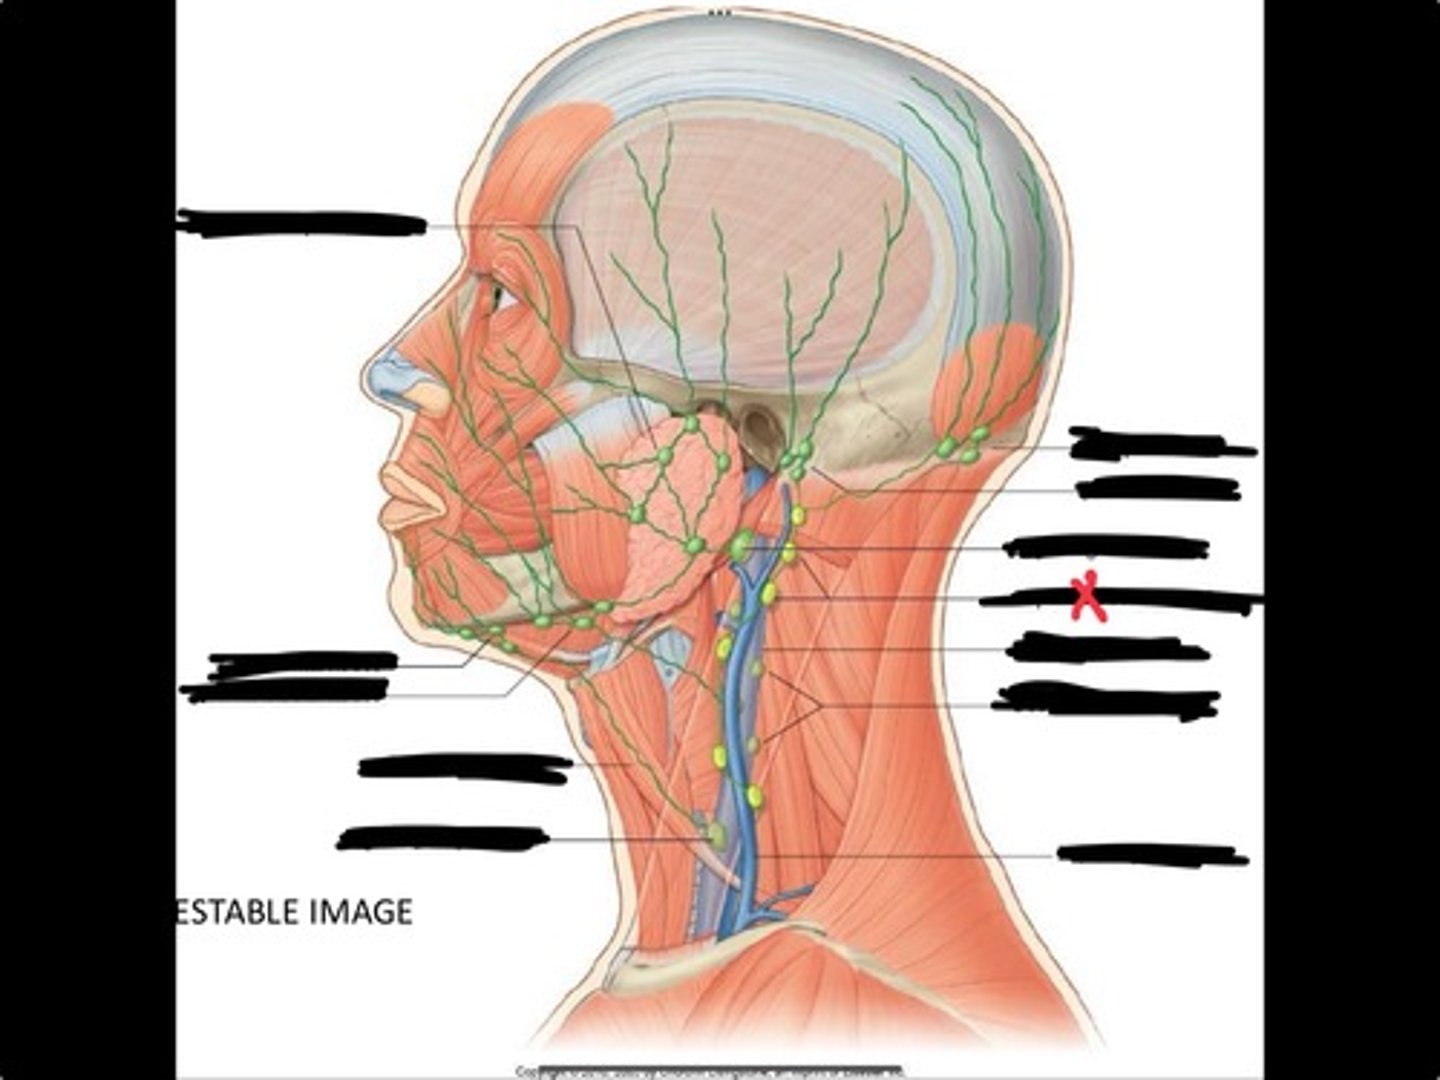

Jugulo-omohyoid node

Submandibular nodes

Submental nodes

Pre-articular/parotid nodes

Occipital nodes

Mastoid nodes

Jugulodigastric nodes

Superficial cervical nodes

Internal jugular vein

Deep cervical nodes

External jugular vein